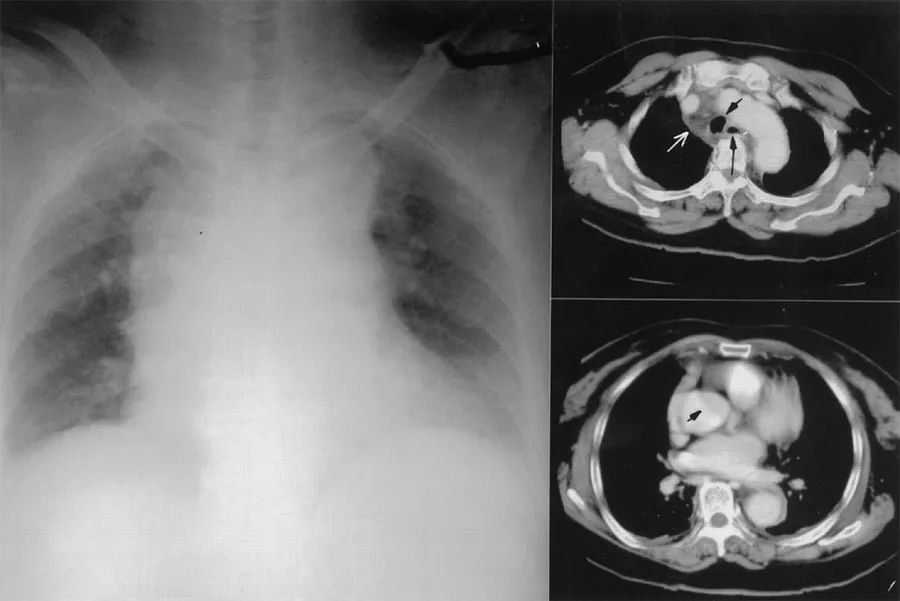

患者女性,79岁,因胸痛、乏力、言语障碍到当地医院急诊就诊,由于心电图、心肌酶正常,胸片显示纵膈轻度增宽,医生疑诊为主动脉夹层。CT检查显示升主动脉上方有“皮瓣”,纵膈的改变被忽略(图3)。患者被诊断为主动脉夹层,收入ICU住院治疗,住院期间患者胸痛有所缓解,但变得虚弱并有咽痛、吞咽问题。

图3 当地医院的影像学检查(右上图白色箭头:纵膈内的浸润灶及液性暗区,短黑箭头:气管,短长箭头:食道;右下图箭头:误诊为主动脉夹层中的内膜瓣)

发病5天后患者被转入上级医院,追问病史发现患者入院前有发热和“感冒”。咽喉检查发现右侧扁桃体肿大,有脓液排出,颈部检查未见明显肿胀或压痛。血液检查显示白细胞增多和高C反应蛋白(290 mg/L),血气显示低氧血症(PO2 67 mmHg),胸片纵膈明显增宽。

再次行CT扫描颈部和胸部,发现右侧扁桃体软组织肿胀,扁桃体周围和咽后间隙多发脓肿并向下延伸至上纵膈(图4)。考虑诊断纵膈炎、脓肿形成,立即插入胸管引流并急诊开胸手术。最终,患者因脓毒症导致多脏器衰竭,在入院第20天死亡。

图4 发病5天后CT(右上图白色箭头:气管周围多个脓肿,短黑箭头:气管,黑长箭头:上腔静脉;右下图白色箭头:脓肿沿降主动脉向下延伸)